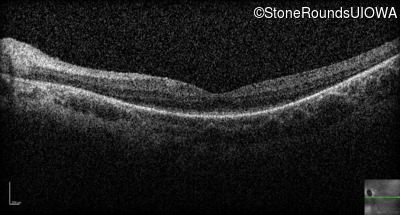

Optical Coherence Tomography - Left - 20/80 -1

Exemplar / OCT Stack

OCT Stack